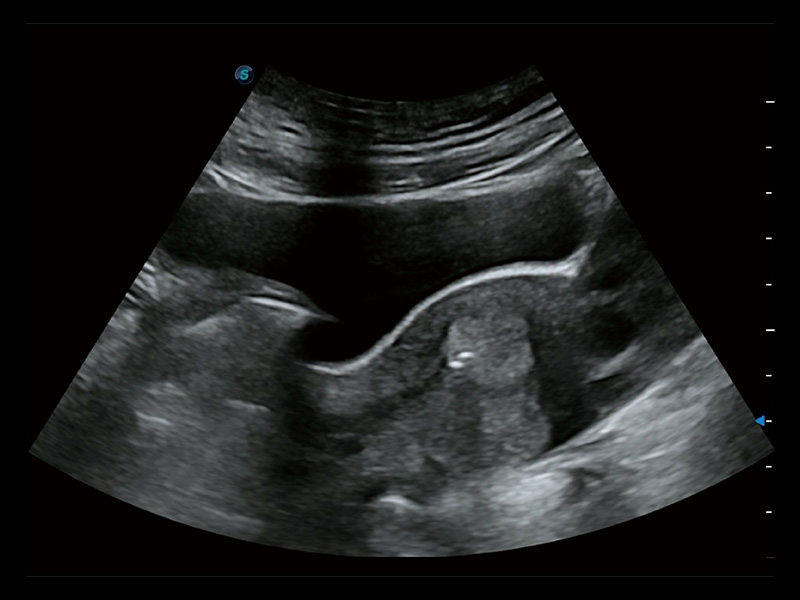

“生育问题”即关系民族复兴,也关系亿万家庭的幸福。随着婚育年龄推迟、社会压力增加等因素,越来越多人群也面临着“生不出、生不好”的问题。辅助生殖作为治疗不孕不育最有效的方法之一,也逐渐成为育儿新希望。而超声检查能为生殖需求人群的初诊评估提供宝贵的信息。 P20 Elite是db真人体育官网匠心打造的一款生殖应用型彩超。她继承db真人体育官网高端极光平台,突破性地将多款新型芯片及硬件模块进行整合,均衡了高端系统性能与小巧灵动机身。P20 Elite卓越的图像质量搭载专科探头,旨在为您提供全面的辅助生殖解决方案。

P20 Elite配备了丰富的生殖探头群和临床应用功能,在卵泡监测、穿刺取卵、胚胎移植、妊娠确认等领域,为生殖需求人群提供了新的临床机会,重新定义高端超声如何应用于生殖健康检查。